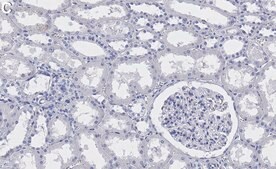

Evaluated by Immunohistochemistry (Paraffin) in Human kidney tissue sections.

Immunohistochemistry (Paraffin) Analysis: A 1:100 dilution of this antibody detected Myosin-9/MYH9 in Human kidney tissue sections.